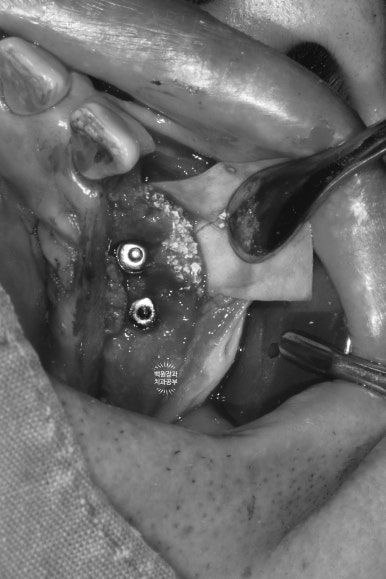

아래는 치아가 하나도 없는 상태셔서... 14개의 치아를 만들어드리기 위해 총 8개의 임플란트를 심어드렸습니다.

센스 있는 분들은 눈치채셨을 수도 있는데, 위 아래의 임플란트가 생긴게 좀 다르죠?

위턱은 잇몸 안에 임플란트가 다 들어가 있는 상태입니다. 뼈이식을 동반하였기 때문입니다.

(뼈이식 재료가 밖으로 쏟아져 나오면 안되잖아요!!)

아래턱의 경우 뼈 상태가 워낙 튼튼하니 좋으셨고, 뼈이식이 많이 필요하지 않아 치유지대주까지 연결해드렸습니다.

즉, 위턱은 임플란트 1차수술까지 진행된 것이고 아래턱은 임플란트 1차수술,2차수술이 한 번에 모두 완료된 상태!